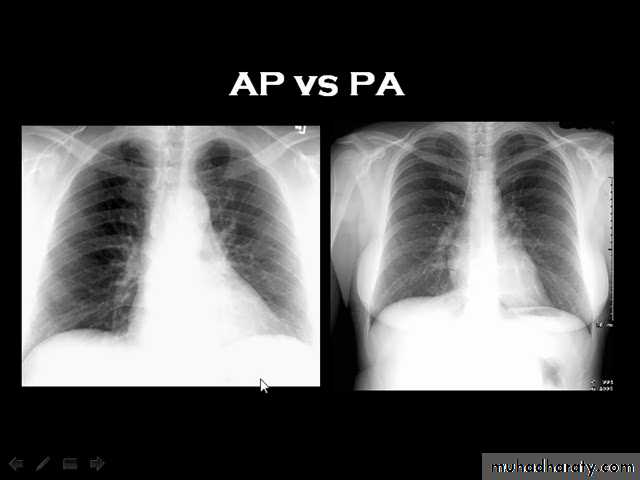

Techniques - Projection

P-A (relation of x-ray beam to patient)

Supine view (AP)

Lateral view .